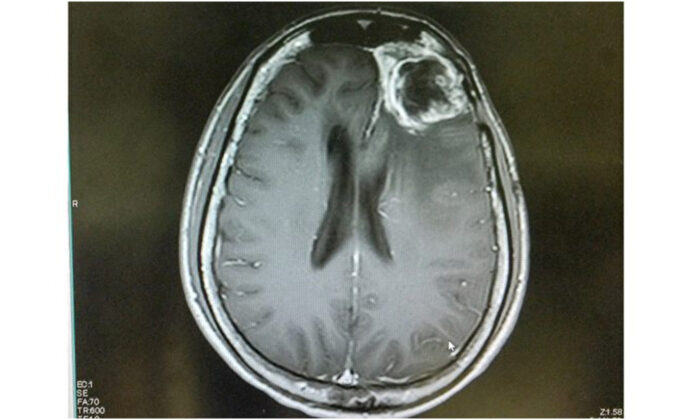

Liệu pháp siêu âm giúp hệ miễn dịch chống lại ung thư não gây chết người

Công nghệ siêu âm xuyên qua hàng rào máu não tạo điều kiện cho hóa trị cũng như liệu pháp miễn dịch trong điều trị u nguyên bào thần kinh đệm.